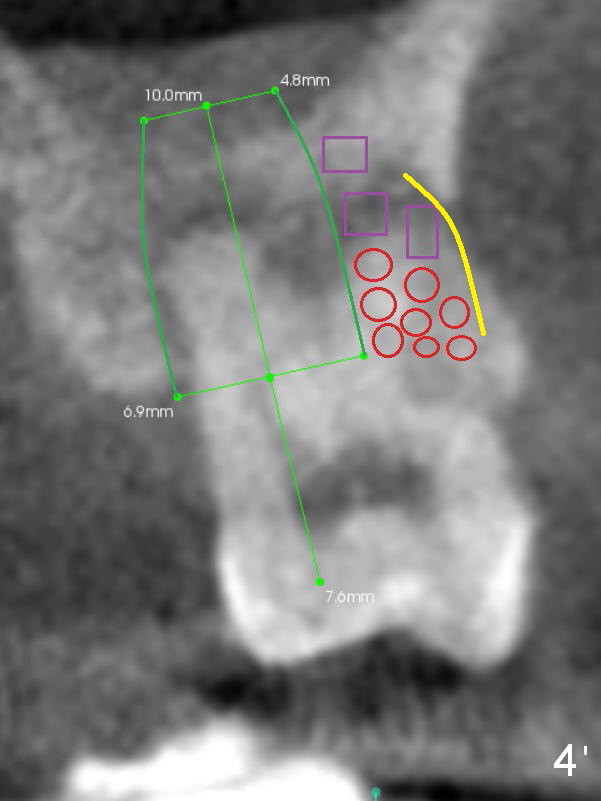

A 42-year-old lady (HJ) has advanced periodontitis at #15 (Fig.1 (CBCT sagittal section)). The buccal (B) plate is thin (Fig. 2 (coronal section), 3 (axial section)). The apical bone is also thin (Fig.1,2). A 7x10 mm implant is placed in a position so that the implant contacts the mesial, palatal and distal walls of the socket (treated with 2% Xylocaine with 1:50,000 Epinephrine) for primary stability (Fig.3). The buccal gap will be filled with Osteogen Plug apically (Fig.4 purple rectangles) and bone graft coronally (red circles). SM implant (Fig.4) is more tapered than UF one (Fig.2), easier to insert.

Open Sinus Master Kit and use 2.8 and 3.6 mm round burs at 2 mm depth to start osteotomy, followed by 4.5-6x14 mm Tatum tapered taps at 11 mm and SM or UF 6.5 mm tap. If stability of the last tap is low, insert a 7 mm implant. If the Sinus Master Kit does not work, try RT2-4. Draw blood after extraction confirms buccal wall defect. Place PRF before Osteogen Plug and bone graft (Fig.4' yellow curved line).